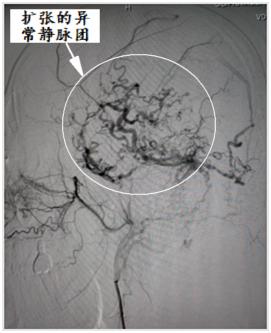

脑病介入科曹骅主任、赵宏廷主治医师先进行左侧颈外动脉血管造影,以明确复杂瘘口,术前造影:颈外动脉中包括枕动脉、耳后动脉、颞浅动脉的多个分支通过硬脑膜向颅内静脉形成异常引流,栓塞术难道很大。

手术过程:术中采取弹簧圈辅助填塞,Onyx液态胶多支供血动脉分次栓塞治疗措施,由于供血动脉纵横交错,手术难道可想而知,经过4小时的艰难努力,于18:30手术结束,术程顺利,成功帮助患者填塞了动静脉瘘,为患者解决了病痛。